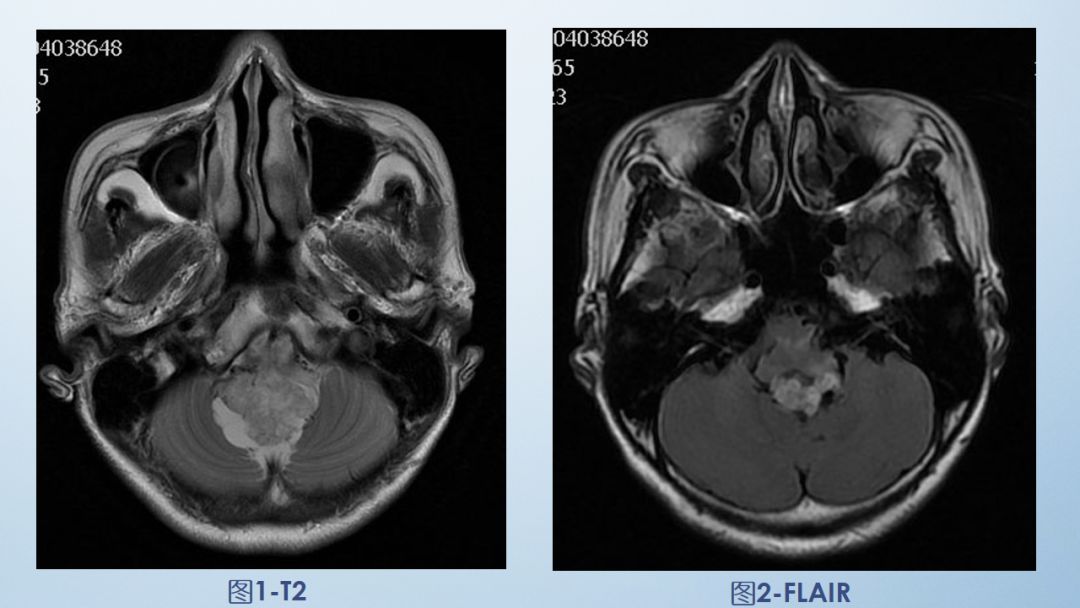

2-FLAIR

FLAIR图及T1矢状位增强:白色箭头所示小脑延髓池内可见实性占位病变,形态不规则,呈分叶状,病变边界清晰,边缘见血管流空信号影如蓝色箭头所示。

影像描述:小脑延髓池内见不规则异常信号影,呈等及稍长T1长T2信号,内部信号不均,边缘见稍粗大流空信号血管影,FLAIR病灶中心少许片状低信号,增强呈明显强化,DWI不均低信号,ADC不均高信号。小脑半球、延髓、第四脑室受压变形。临近延髓受压变窄,呈长T1长T2信号。